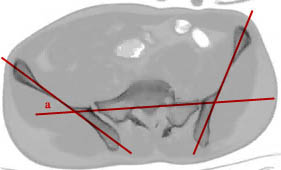

He then showed some representative CT scans with lines drawn on them similar to what is shown below.

I can find no references about this quantitative method (iliosacral or quad_sacral lines or angles) of determining whether or not there is a transverse plane posterior deformity and how big it might be. How exactly are these lines drawn? Are there any normal values for the angles of their intersection?